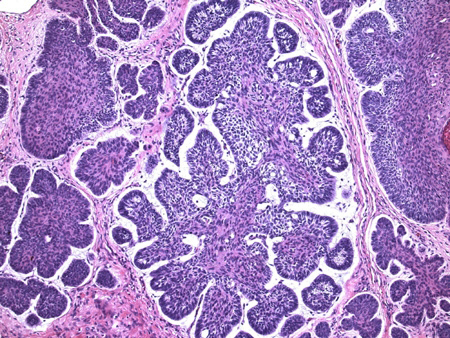

O diagnóstico histopatológico do CBC normalmente é simples. Ocasionalmente, pode ser desafiador diferenciá-lo de outras neoplasias, como o tricoepitelioma. O CBC se manifesta como massas dérmicas de formas e tamanhos variados compostas por células basofílicas uniformes, com um grande núcleo oval e citoplasma reduzido. Essas massas geralmente estão associadas à epiderme ou a uma abertura folicular, e têm uma camada celular periférica com os núcleos dispostos em paliçada.[3]Raasch BA, Buettner PG, Garbe C. Basal cell carcinoma: histological classification and body-site distribution. Br J Dermatol. 2006 Aug;155(2):401-7.

[5]Barnhill RL, ed. Textbook of dermatopathology, 2nd ed. New York: McGraw-Hill Medical; 2004.[Figure caption and citation for the preceding image starts]: Observam-se aparência histológica do carcinoma basocelular (20x, coloração H-E), divisão estroma-epitélio, distribuição característica dos núcleos em paliçada periférica, além da assim chamada natureza mucinosa do estromaDo acervo de Drazen M. Jukic, MD, PhD [Citation ends].

O CBC é uma das neoplasias humanas com maior taxa mitótica (alta atividade mitótica), mas também tem uma alta taxa apoptótica. Assim, a neoplasia tem um crescimento lento de modo geral, e ambos os elementos (figuras mitóticas e apoptóticas) são usados como um dos critérios diferenciadores para o diagnóstico de CBC. Em uma pequena porcentagem dos casos, os CBCs são pigmentados e, clinicamente, podem parecer um melanoma.[3]Raasch BA, Buettner PG, Garbe C. Basal cell carcinoma: histological classification and body-site distribution. Br J Dermatol. 2006 Aug;155(2):401-7.